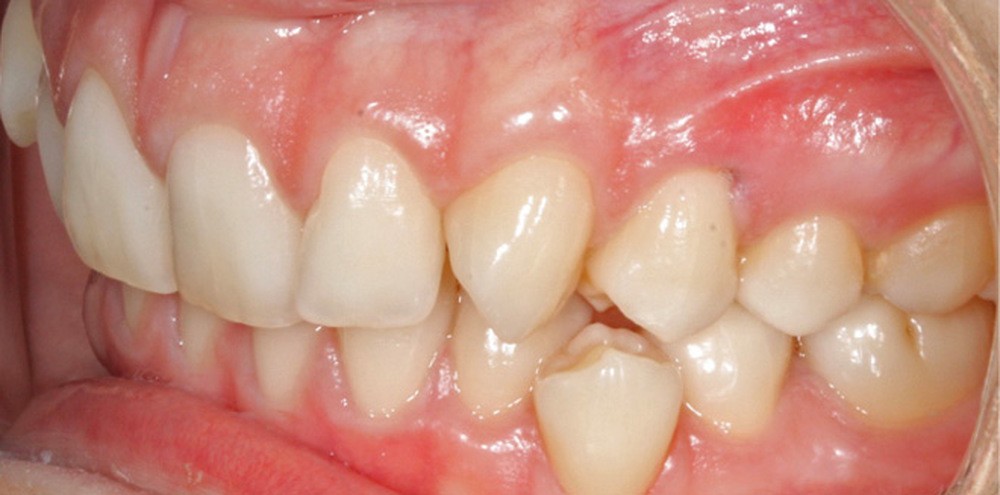

L’examen intra-arcade met en évidence une hygiène bucco-dentaire irréprochable, favorable à un traitement en technique linguale. Le phénotype parodontal est fin dans la région incisivo-canine mandibulaire. L’encombrement est estimé à 8 mm à la mandibule et à 4 mm au maxillaire (fig. 1). Les arcades ont des formes similaires, en U. Les rapports inter-arcades mettent en évidence une classe 1 d’Angle molaire, une classe 2 d’Angle canine et une supraclusion antérieure (recouvrement : 5 mm ; surplomb diminué). Les milieux inter-incisifs sont déviés entre eux avec une origine mixte (= 1,5 mm) (fig. 2).